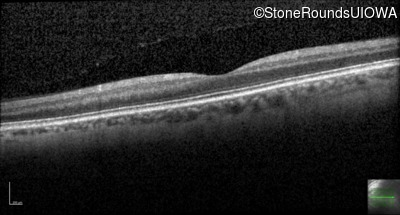

Optical Coherence Tomography - Left - 20/200

Exemplar / OCT Stack

OCT Stack